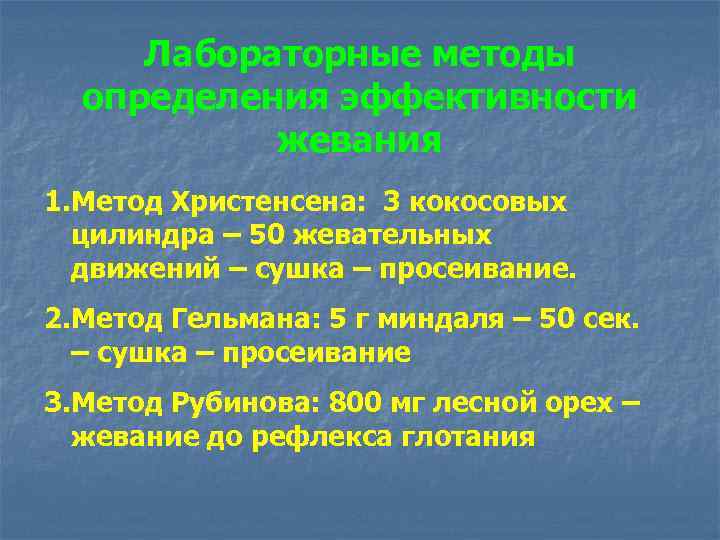

Методы определения функционального состояния зубочелюстной системы -Клинические (основаны на оценке состояния каждого зуба) -Лабораторные -Графические

Лабораторные методы определения эффективности жевания 1. Метод Христенсена: 3 кокосовых цилиндра – 50 жевательных движений – сушка – просеивание. 2. Метод Гельмана: 5 г миндаля – 50 сек. – сушка – просеивание 3. Метод Рубинова: 800 мг лесной орех – жевание до рефлекса глотания